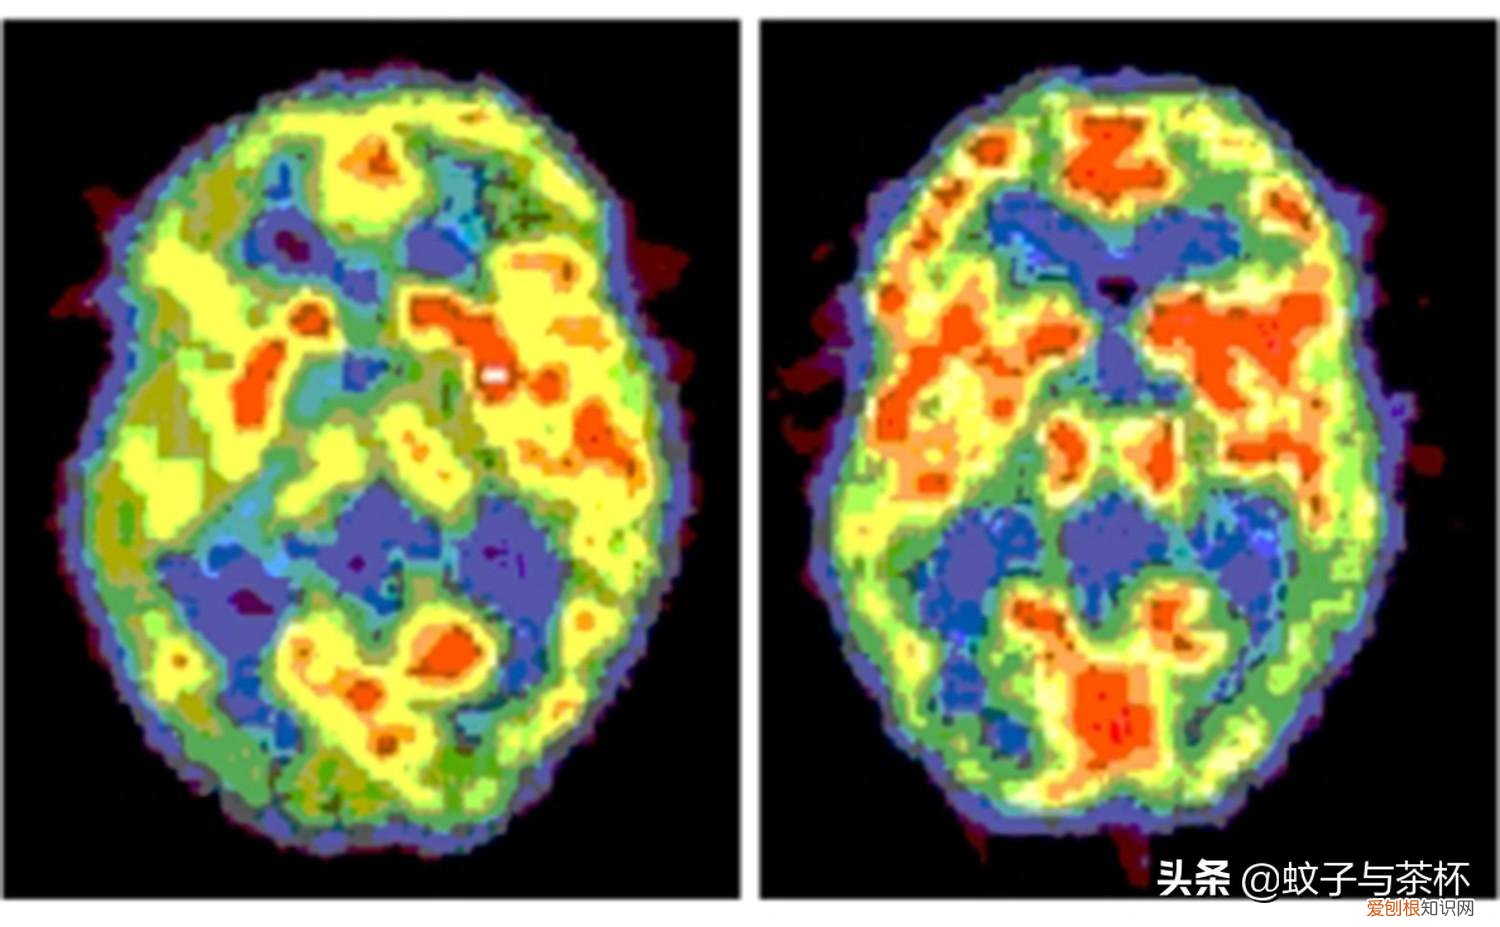

比如通过对大脑电信号的采集和研究,人们逐渐发现,梦与睡眠时相中的快速动眼睡眠期(REM)高度相关 。